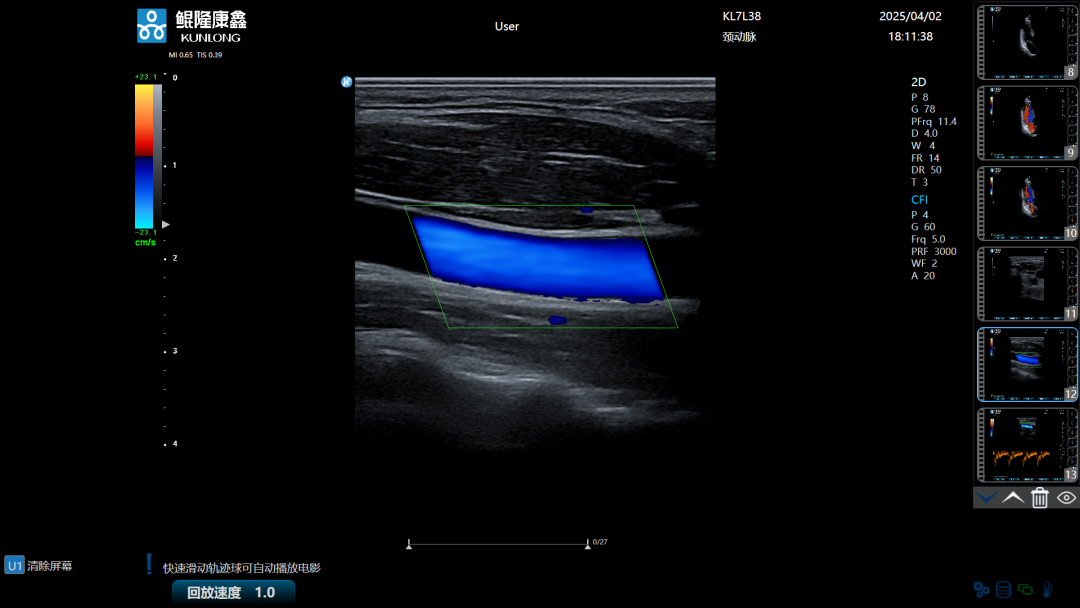

据悉,鲲隆康鑫自主研发的彩色多普勒超声诊断仪是一款集成了先进超声成像技术的创新型医疗设备,该产品凭借128通道数字波束形成技术,实现斑点追踪、组织多普勒成像等多种高级成像功能,具有图像清晰、功能全面、操作便捷等特点,在关键技术指标上已接近国际主流水平,可用于腹部、心脏、血管、妇产等临床诊断,为临床医生提供更精准、更高效的诊断依据。

作为“包河智造”的本土代表性成果,“彩色多普勒超声诊断仪”的量产上市不仅填补了省内超声影像诊断设备领域的技术空白,更以国际主流水平的成像性能、仅为进口产品60%-70%的价格,有望打破进口品牌长期垄断的局面,带动省内精密制造、电子信息等相关产业链企业的协同发展。